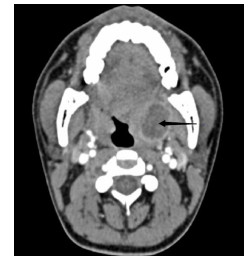

1 资料与方法患者,男,22岁,因“咽痛16 d ”于2020年6月19日就诊于浙江大学医学院附属第二医院耳鼻喉科。起初未就医,近半个月来咽痛逐渐加重,伴左侧耳朵放射痛,吞咽时明显,不能言语,伴张口困难,进食困难,夜间平卧时偶感呼吸不畅。来院前1 d,患者曾有吐出脓血性液体。查体见张口度1.5指,双侧软腭隆起,充血,双侧扁桃体Ⅱ度,右侧扁桃体后方可见少许脓液流出。急诊行颈部增强CT(图 1)示:双侧扁桃体炎伴周围脓肿形成,右侧脓腔可见积气。尝试行左侧扁桃体周围脓肿穿刺,未及明显脓液。收住入院后予头孢哌酮舒巴坦抗感染及甲泼尼龙抗炎消肿治疗,患者感咽痛逐渐缓解,软腭肿胀逐渐减轻。入院后第5天,再次行颈部增强CT(图 2)示:左扁桃体脓肿扩大,右侧扁桃体内脓肿消失,局部轻度肿胀。予行左侧扁桃体周围脓肿穿刺及切排,流出较多脓液。切排后,继续予上述药物治疗,每日定期扩张切排口,入院后第7天,切排口已无明显脓液,复查颈部增强CT(图 3)示:左侧脓肿基本吸收、残留少许气体。入院后第8天,患者予出院。后经短期随访,患者恢复情况可,无症状反复。目前患者已失随访,本研究经医院伦理委员会审批免除知情同意,批件号:(2020)伦研审第(979)号。

| 图 1 患者2020-06-20颈部C增强CT(箭头示双侧扁桃体周围脓腔形成) |